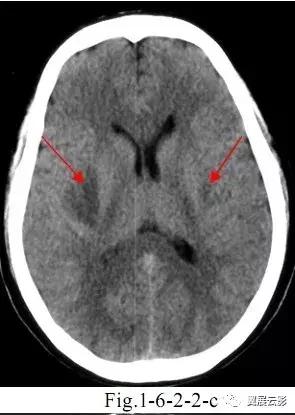

病例3:多发腔隙性脑梗死

腔隙性脑梗死为深部脑组织的小面积梗死,好发部位为基底节,丘脑,脑干,小脑及脑室旁白质区。应写清病灶的部位,大小,数目,鉴别诊断时应关注与脑血管周围腔隙相鉴别。